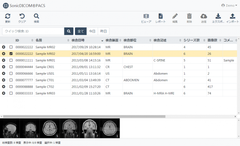

リスト画面

SonicDICOM PACSは、検査装置で発生した画像を受信・管理する「DICOM(*1)サーバー」と、それらの画像を参照する「DICOMビューア」の2つの機能を備えたソフトウェア〔PACS(*2)〕です。

今回のバージョンでは、以前より要望の多かった多言語対応を実装し、日本語をはじめ8カ国語に対応します。またリストやツールバーなどのカスタマイズ機能やアカウント毎の権限設定などを実装し、使いやすさとセキュリティ面を更に強化しました。